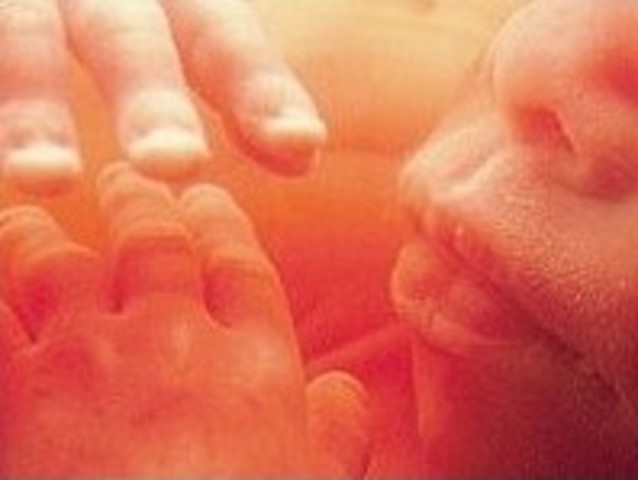

The legs and arms are growing and the elbow and toes are visible.The feet and hand buds appear.

The fingers and toes are vetu define. The bones atart to form.